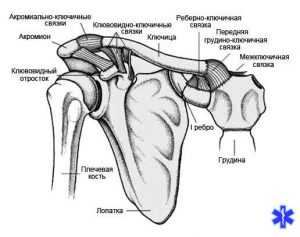

Анатомия

Ключичная кость, имеет s-образную форму и прощупывается при пальпации в зоне надплечья. Функция косточки заключается в контроле плечевого сустава, она помогает фиксировать его, а также берет на себя часть физических нагрузок, выполняемых рукой.

Ключицу условно можно разделить на три отдела:

Ключичный отдел представляет собой сложную анатомию, так как соединен с сосудистыми и нервными окончаниями, находящимися за костью и верхней частью легких.

Ключица представляет собой трубчатую кость немного изогнутой формы, похожей на ключ, отчего она и получила своё название. Медики выделяют три части. Один конец соединяется с грудиной, другой с лопаткой, и середина между ними. Кость достаточно тонкая, ломается быстро. Прикрепление к другим костям осуществляется жёстко, при ударе нет амортизации, что делает ключицу особенно уязвимой при ударе или падении.

Ключица представляет собой трубчатую изогнутую кость, которая входит в состав плечевого пояса. Именно эта кость обеспечивает фиксацию верхней конечности к туловищу. Кость имеет S-образную форму, верхнюю и нижнюю поверхность, акромиальный и грудинный конец. Верхняя поверхность гладкая, а нижняя содержит образования, которые необходимы для прикрепления связок, прохождения сосудов и нервов.

Образует ключица и два сустава: акромиально-ключичный и грудино-ключичный, которые укреплены многочисленными связками. К ключице прикрепляются многочисленные мышцы плечевого пояса. Рядом расположены крупные сосуды, в непосредственной близости подключичная артерия и вена. Под костью проходит сосудисто-нервный пучок, верхний полюс легкого.

Ключица – небольшая, слегка изогнутая трубчатая кость, расположенная над верхним ребром и соединяющая грудину с лопаткой. Служит для укрепления плечевого пояса, является опорой для лопатки и костей верхней конечности. Защищает нервы и крупные сосуды подмышечной области.

Локализация перелома в значительной степени определяется анатомическими особенностями кости. Чаще всего ключица ломается в средней трети ближе к акромиальному концу – в наиболее тонком и изогнутом отделе. Другими факторами, влияющими на расположение повреждения, являются направление и точка приложения травмирующей силы.

Самыми распространенными являются оскольчатые и косые переломы. Под влиянием тяги мышц и веса конечности периферический фрагмент ключицы смещается книзу, кнутри и кпереди. Одновременно грудино-ключичная мышца «утягивает» центральный отломок вниз и назад. В результате надплечье укорачивается. Иногда конец периферического отломка продвигается в зону расположения сосудисто-нервного пучка, это представляет опасность из-за угрозы повреждения нервов и кровотечения.